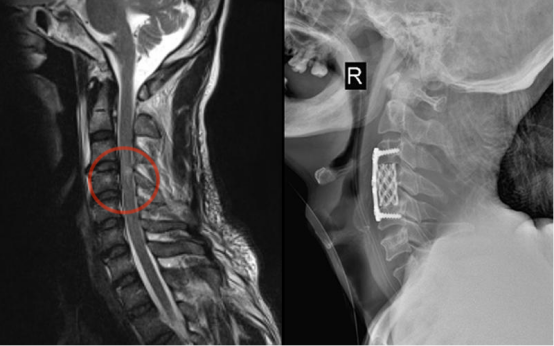

2.下颈椎

⑴颈椎前路手术:椎间盘切除Cage椎间融合术;椎体次全切椎管减压钛笼钛板内固定术。⑵颈椎后路手术:后路单开门、双开门椎管扩大成形术;侧块螺钉钉棒内固定术。⑶颈椎前后路联合手术,一期完成治疗复杂性颈椎病。

图注:手术前MRI显示多节段颈椎间盘突出、椎管狭窄、脊髓受压,手术予颈4椎体次全切除,钛笼植入钛板内固定。